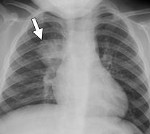

Почему развивается очаговая (сливная) пневмония

Очаговая пневмония — это воспалительный процесс легких, в основном альвеолярной или интерстициальной ткани, который, в отличие от лобулярной пневмонии, поражает только ограниченный участок легочной ткани: один или несколько сегментов легкого. Небольшие поражения могут сливаться вместе и образовывать сливную пневмонию, которую сложнее лечить. Классификация МКБ-10: позиции J12-J18. Причины возникновения Этиология пневмонии делится на несколько форм. Первичные …